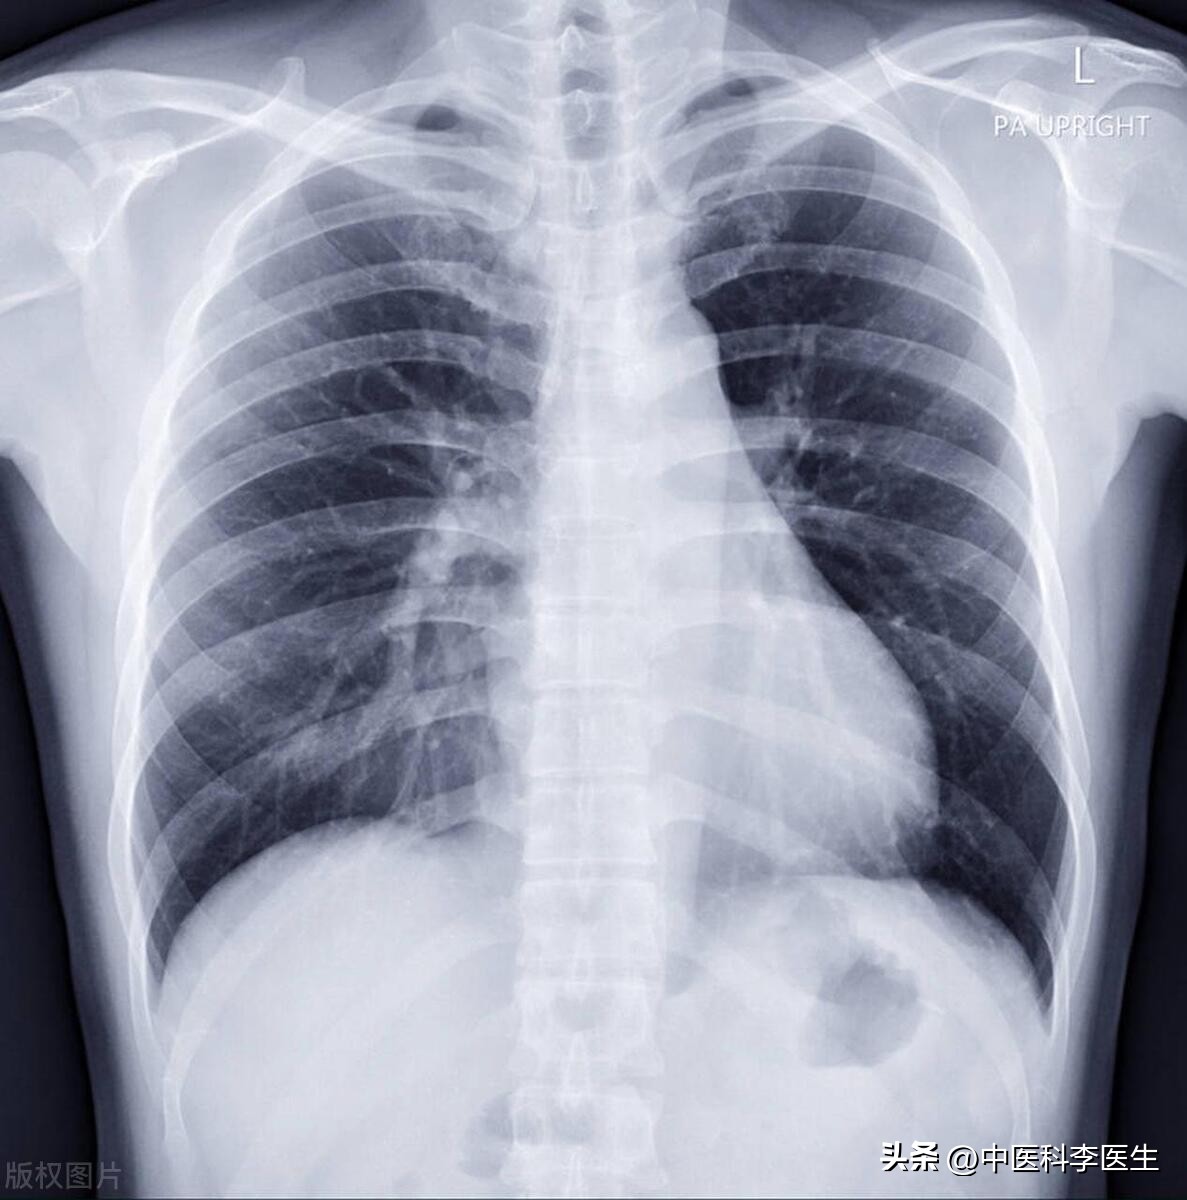

病毒在下呼吸道,不小心就会白肺。